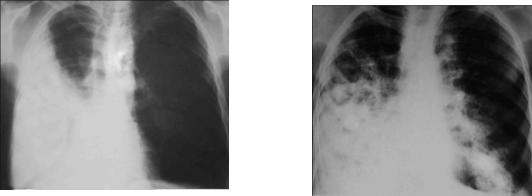

К числу осложнений ВП относятся: а) плевральный выпот (рис.1-4); б) эмпиема плевры;

в) деструкция/абсцедирование легочной ткани (рис.1-5); г) острый респираторный дистресс-синдром; д) острая дыхательная недостаточность; е) септический шок;

Рис. 1-4. Правосторонний Рис. 1-5. Полисегментарная деструкэкссудативный плеврит тивная пневмония с локализацией в средней и нижней долях правого лег -

кого и нижней левого.